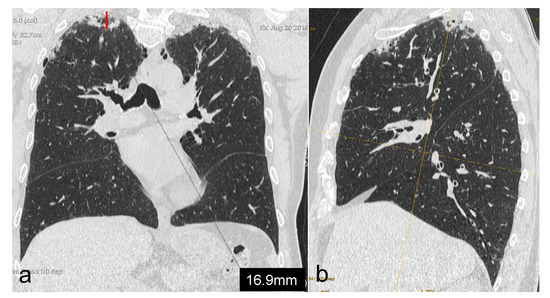

For each region, a dichotomous score (0–1) was assigned according to the presence or absence of PPFE alterations. Moreover, we measured the maximum depth of the fibrotic involvement of the parenchyma of both lungs from the pleural plane, regardless of the region analysed; this was performed through multiplanar reconstructions, coronal oblique imaging and imaging that was perpendicular to the pleural plane itself. Then, we assigned a score as follows (Figure 1):

Figure 1. Measurement (a) of maximum extension of PPFE-like lesions from the pleural plane into lung parenchyma, by using multiplanar reconstructions, coronal oblique and imaging perpendicular to the pleural plane (b).